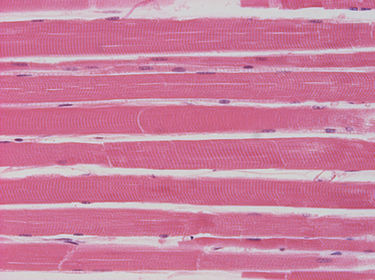

Tejido muscular (esquelético)

Tejido muscular (cardíaco) con estriaciones núcleos visibles